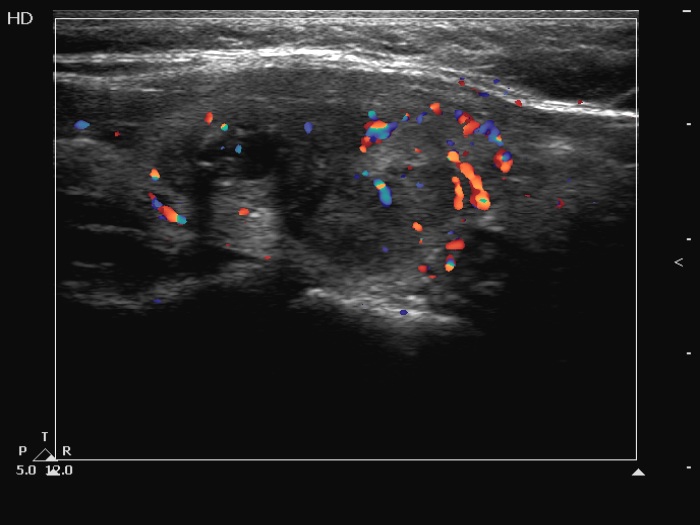

Left lobe, another longitudinal scan, color Doppler mode. The intranodular vascularity is increased.